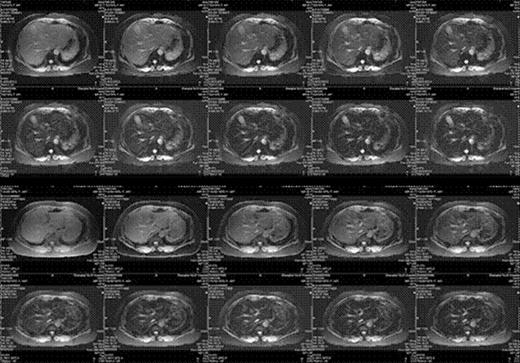

Before DFO treatment, a patient had an abnormal liver function. Along with iron chelation therapy, his LPI decreased rapidly. Meanwhile, his ALT dropped and his hemoglobin increased gradually. Furthmore, his LIC decreased after receiving DFO treatment.

Lane a: LIC was 9.97mg/g dry weight on week 0.

Lane b: LIC was 5.81mg/g dry weight on week 26.

The improvement of ALT, hemoglobin and LIC